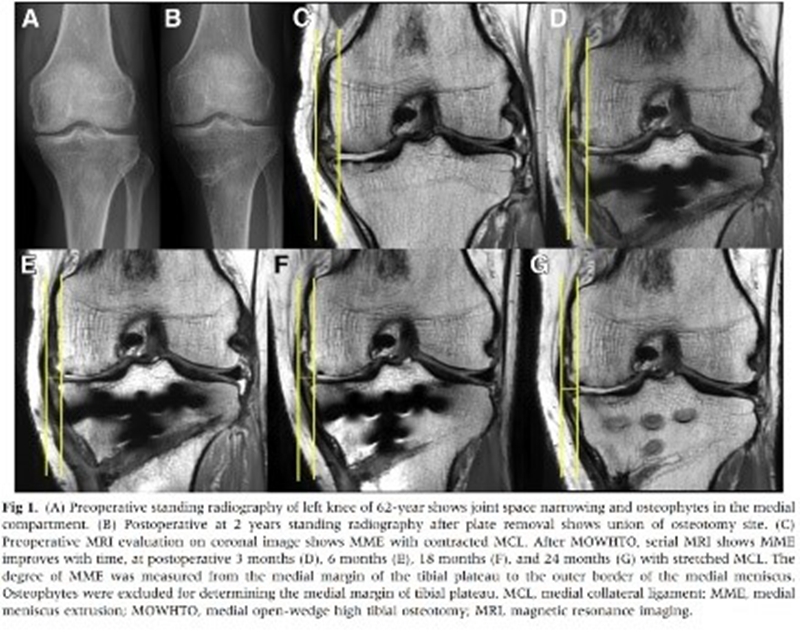

Jung等人分析了26例内侧开放楔形胫骨高位截骨术(MOWHTO)患者,在术前和术后3个月、6个月、1.5年和2年使用MRI测量内侧半月板挤压情况。发现术后6个月内侧半月板挤压情况显著改善,随着时间的推移,情况进一步改善,术前胫骨近端内侧角(MPTA)和术后内侧半月板挤压情况显著相关[1]。

图1